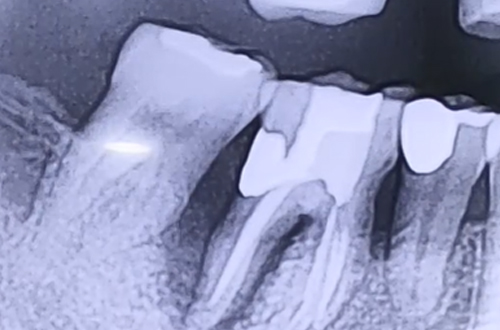

BEFORE

AFTER

치료 유형 발치 후 임플란트

어금니 부분의 통증과 불편함을 호소하며 내원하신 환자분이십니다.

해당 환자분의 경우 어금니 쪽에 음식물이 잘 끼는 편이라 하셨는데요.

그 부분을 살펴보니 잇몸이 안 좋아지면서 점점 높이가 내려가

어금니 사이의 틈새가 넓어지게 된 것이 원인으로 보였습니다.

문제가 된 어금니가 예전에 신경치료를 받은 곳이기 때문에

통증과 불편함에 대한 감각이 적어 대응이 늦었다고 보입니다.